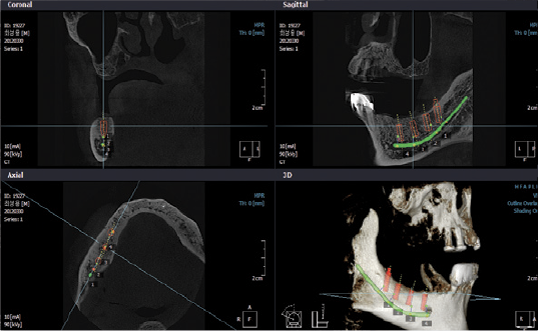

- Pianificazione terapeutica mediante trattamenti implantari

- Programmazione di chirurgia implatare guidata